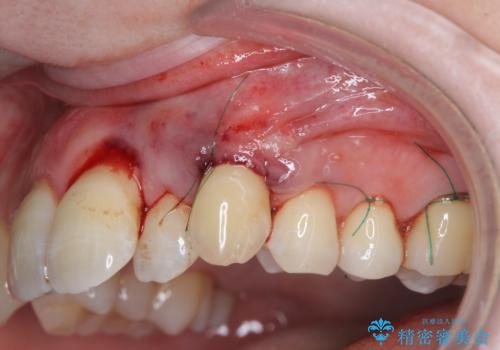

目立つ八重歯の歯ぐきのさがり 根面被覆による改善

- 長年気になっていた歯ぐきのさがり(歯肉退縮)の相談で来院されました。

ブラッシング指導をまず行い、硬すぎる歯ブラシを使用しないこと、歯ブラシの当て方を確認しました。

プラークコントロールが十分に行えるようになったのち、結合組織移植を用いた根面被覆手術を行います。

手術は静脈内麻酔下で行いほとんど記憶もない状態で終えることができます。

良好な結果が得られ、大変満足いただくことができました。